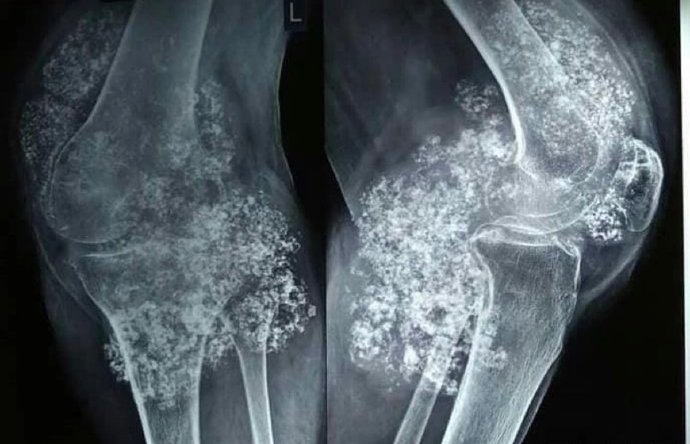

一例罕见的膝关节滑膜骨软骨瘤病

医生介绍,滑膜软骨瘤病又称滑膜软骨化生,是一种不常见的良性关节病

滑膜软骨瘤病也称为滑膜骨软骨瘤病

膝关节滑膜软骨瘤病